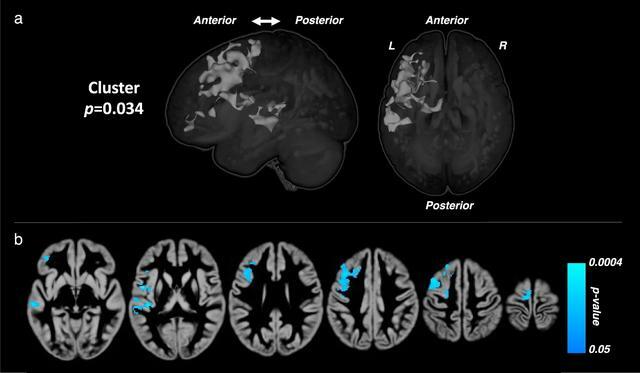

Mauras博士和DirecNet調查人員招募了42名14至17歲的青少年,他們在8歲前被診斷為1型糖尿病,並正在接受胰島素治療。這些青少年被隨機分配到兩組中的一組--一組使用混合閉環胰島素輸送系統,另一組接受標準糖尿病護理。研究人員在六個月的研究期前後對所有參與者進行了認知評估和多模式腦成像。

使用閉環血糖控制系統的參與者在表明正常青少年大腦發育的關鍵大腦指標方面比標準護理組有明顯的改善--換句話說,他們的結果更接近那些沒有糖尿病的青少年。閉環組還顯示出更高的認知(IQ)結果和大腦功能活動,更符合正常青少年的大腦發育。